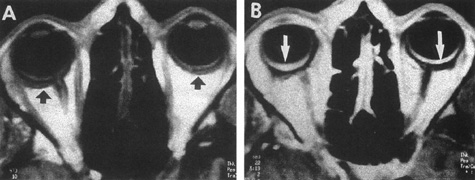

Intracavernous carotid aneurysms constitute only 2% to 3% of all intracranial aneurysms and are unique because of their location. These aneurysms arise from the internal carotid artery as it traverses the cavernous sinus4 (Fig. 3) and therefore produce a specific constellation of ocular and neurologic signs and symptoms. Rupture of such aneurysms, which are almost always saccular, may possibly result in carotid–cavernous sinus fistula, but subarachnoid hemorrhage is rare.5 However, slowly progressive enlargement is the rule, usually occurring within the cavernous sinus, with compression of the third, fourth, and sixth cranial nerves and later involving the first and second divisions of the fifth nerve (see Chapter 12).6 Progressive enlargement of the aneurysm forms a mass in the floor of the middle cranial fossa, compromising motor as well as sensory functions of the trigeminal nerve. Anterior expansion of the aneurysm erodes the anterior clinoid, optic foramen, and superior orbital fissure, eventually producing unilateral visual loss and exophthalmos. Posterior expansion, which occurs later, can erode the petrous portion of the temporal bone, causing ipsilateral facial palsy and, rarely, deafness. The sphenoidal sinus and the nasopharynx may infrequently be involved by inferior expansion and medial extension erodes into the sella and may simulate a pituitary tumor7 or cause bilateral ophthalmoplegia.8 Bilateral saccular intracavernous aneurysms occur uncommonly.9

Fig. 3. Magnetic resonance images of intracavernous aneurysm in a 72-year-old woman with left retrobulbar pain and sixth-nerve palsy. A: Coronal section (TR, 800 ms; TE, 30 ms). B: Parasagittal section (TR, 1000 ms; TE, 20 ms). C: Axial section (TR, 800 ms; TE, 30 ms). Note partial occlusion by thrombus (T). D: In a similar patient, carotid arteriogram (subtracted, lateral view) demonstrates a large intracavernous aneurysm.

Intracavernous aneurysms are suspected by the clinical presentation of a chronic cavernous sinus syndrome and are diagnosed by enhanced computed tomography (CT), magnetic resonance imaging (MRI), and arteriography (see Fig. 3). Because of the location and configuration within the cavernous sinus, direct surgical approaches to cavernous carotid aneurysms are hazardous. In recent years intravascular occlusion of the internal carotid by detachable balloon has evolved as a safe and successful procedure, often with relief of pain and improvement in ophthalmoplegia.10 Unfortunately, these balloons are commercially unavailable at the time of this writing.